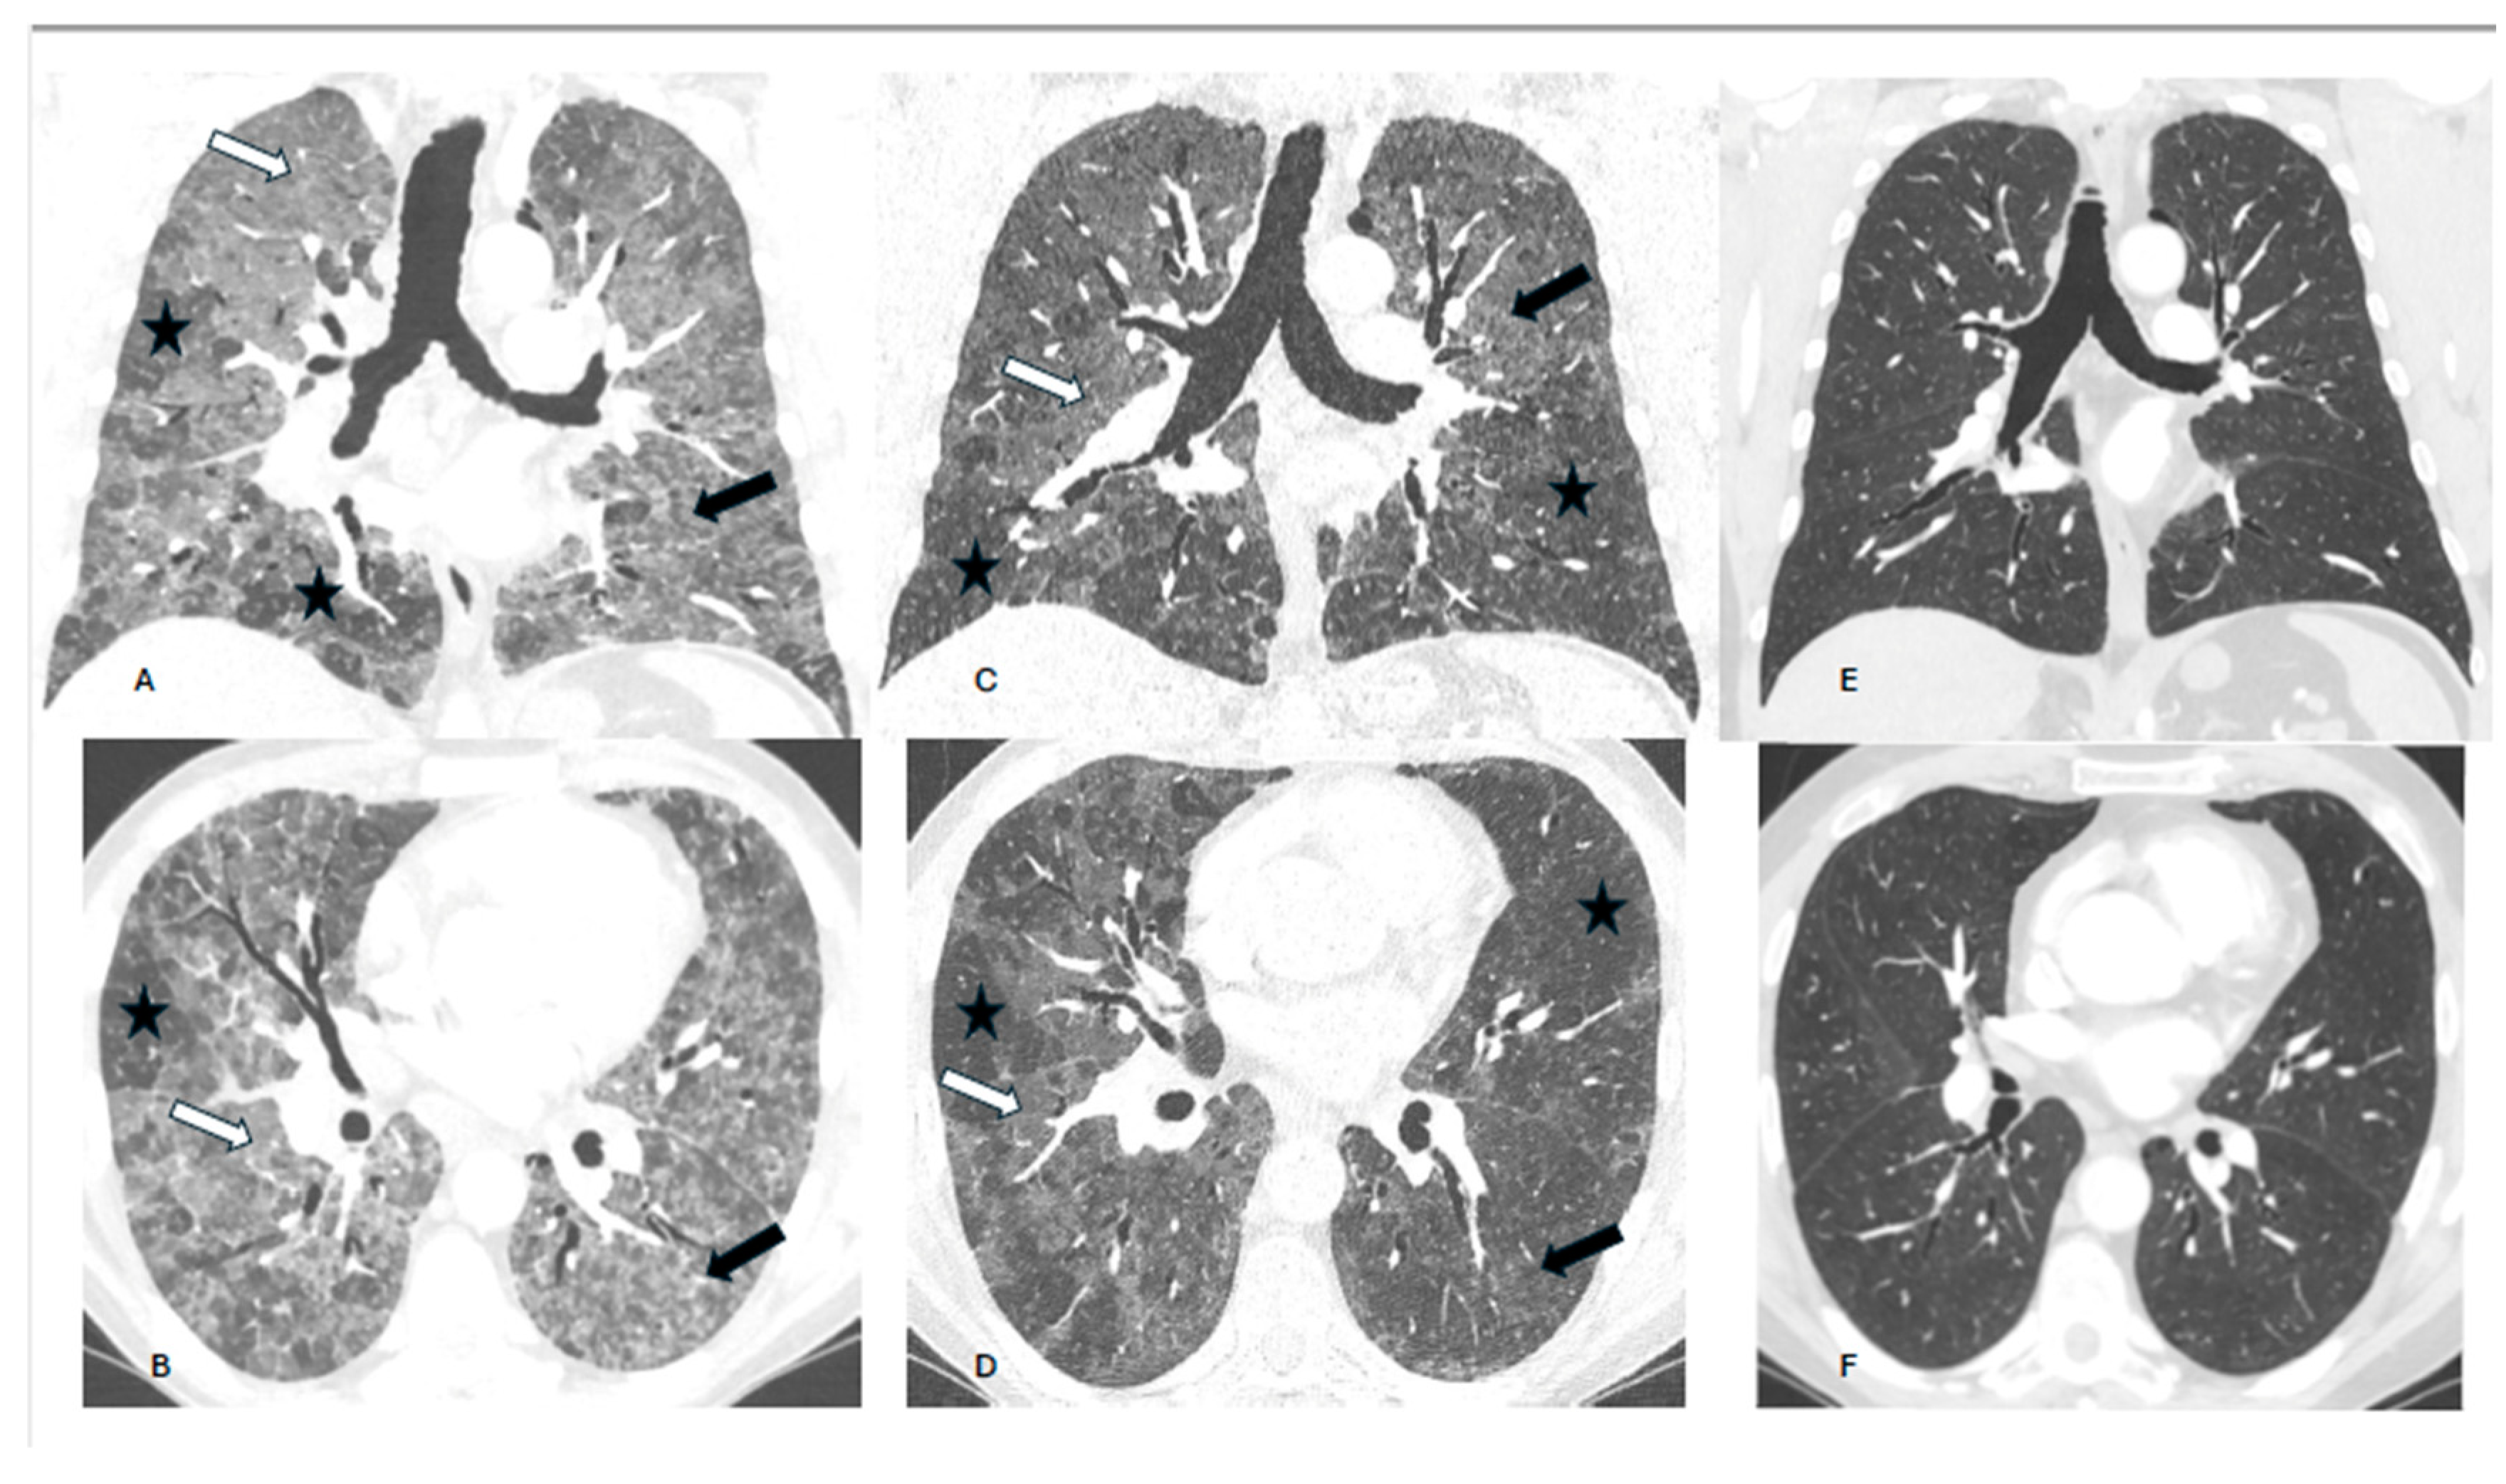

Background. Hypersensitivity pneumonitis (HP) is an increasingly recognized interstitial lung disease, developing as a result of exposition to inhaled, mostly organic, antigens. Two types of the disease are presently distinguished based on HRCT pattern and/or lung biopsy: fibrotic and non-fibrotic (non-fHP). Complete antigen avoidance is the principle of non-fHP treatment. The indications for steroids use in non-fHP depend on the clinical course of the disease. Case presentations. We present three patients in whom acute respiratory failure was diagnosed as the first sign of non-fHP. Intravenous prednisolone, followed by oral therapy with prednisone in diminishing doses, resulted in marked clinical improvement. Respiratory failure subsided within a few days, but regression of lung opacities lasted from 3 to 7 months. In one patient, the discrete reticular opacities, suggestive of the early phase of lung fibrosis, were present on HRCT, but complete regression of lung disease was achieved in the course of treatment. The patients were instructed to avoid antigens exposure; nevertheless, in one of them, a relapse of the disease, requiring a temporal increase of prednisone dose, was observed. Conclusions. Non-fHP may present as sudden-onset hypoxemic respiratory failure. In such patients, the diagnosis is based on medical history concerning the exposition to inciting antigens and characteristic HRCT pattern. Intravenous therapy with prednisolone results in quick resolution of respiratory failure, and BAL performed with a few days of delay may still be of diagnostic value. Ground glass opacities and air trapping may persist for months from exposure.